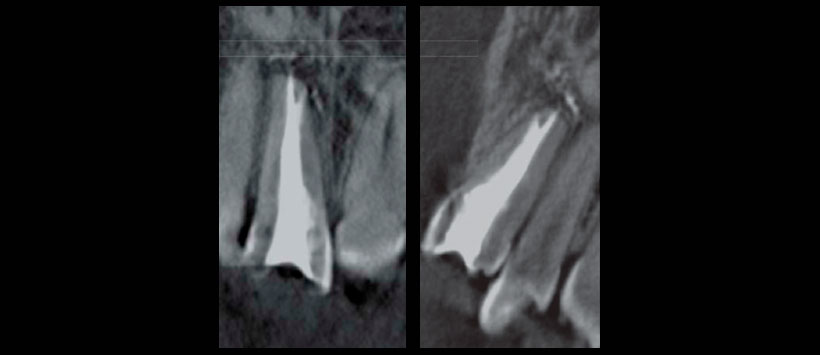

Previo a la segunda cita se evaluó con la tomografía cone-beam y se confirmó la desviación del conducto así como la presencia de una perforación (Figura 2), lo que permitió planificar la dirección que se debía seguir para retomar el conducto principal y eliminar el poste y material de obturación. Esto no fue posible de detectar con la radio- grafía convencional debido a la angulación que éste seguía.